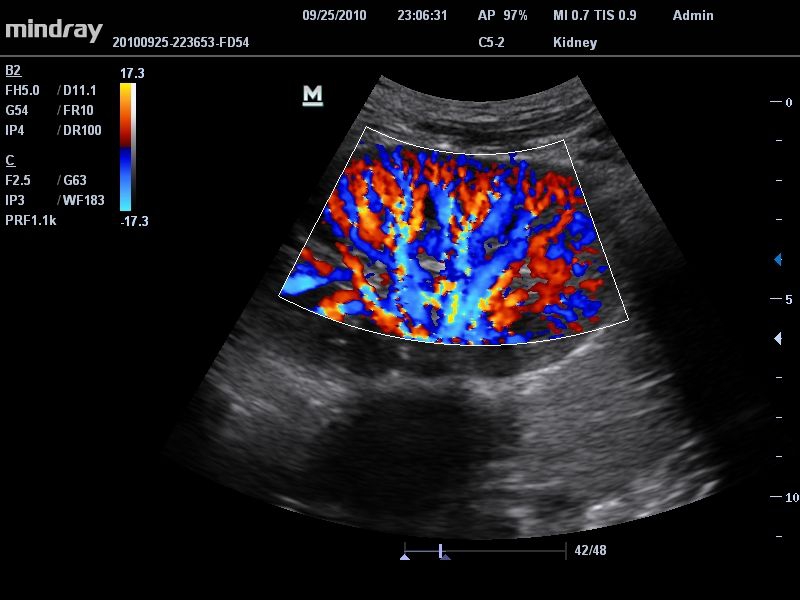

Mindray DC-T6

Ультразвуковая система Mindray DC-T6 – это инновационный аппарат для проведения высокого уровня диагностики с качественной визуализацией и широким спектром применения. Платформа рекомендована для использования в коммерчески многопрофильных медицинских учреждениях и государственных лечебных клиниках.

Цветовой допплер:

Да

• Режимы сканирования: B/M/CFM/PDI/Направленный PDI/PW, HPRF, Тканевая гармоника, М- и цветной М-режим.